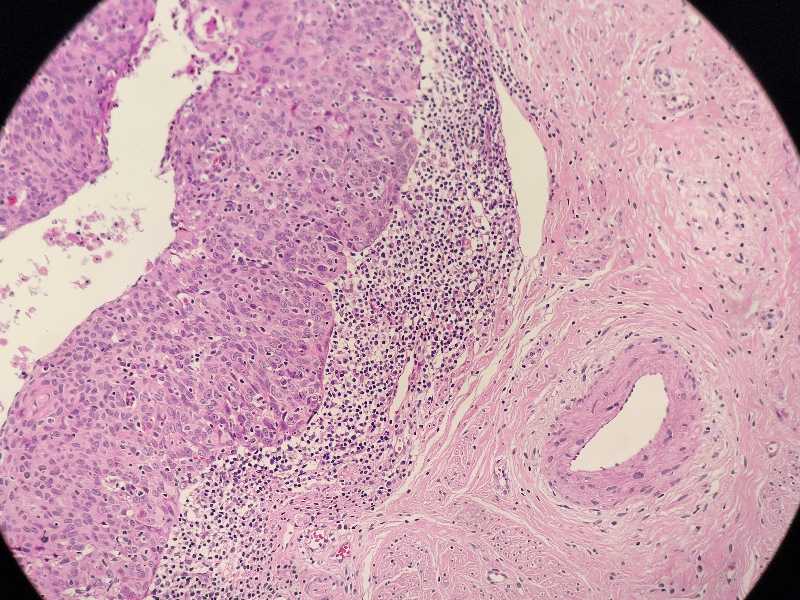

女40岁宫颈锥切组织浸润还是CIN累腺

女40岁宫颈锥切组织 浸润还是CIN累腺?

考虑:鳞癌